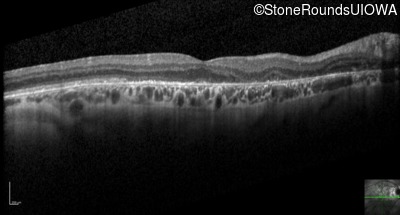

Optical Coherence Tomography - Right - 20/100 +1

Exemplar / OCT Stack